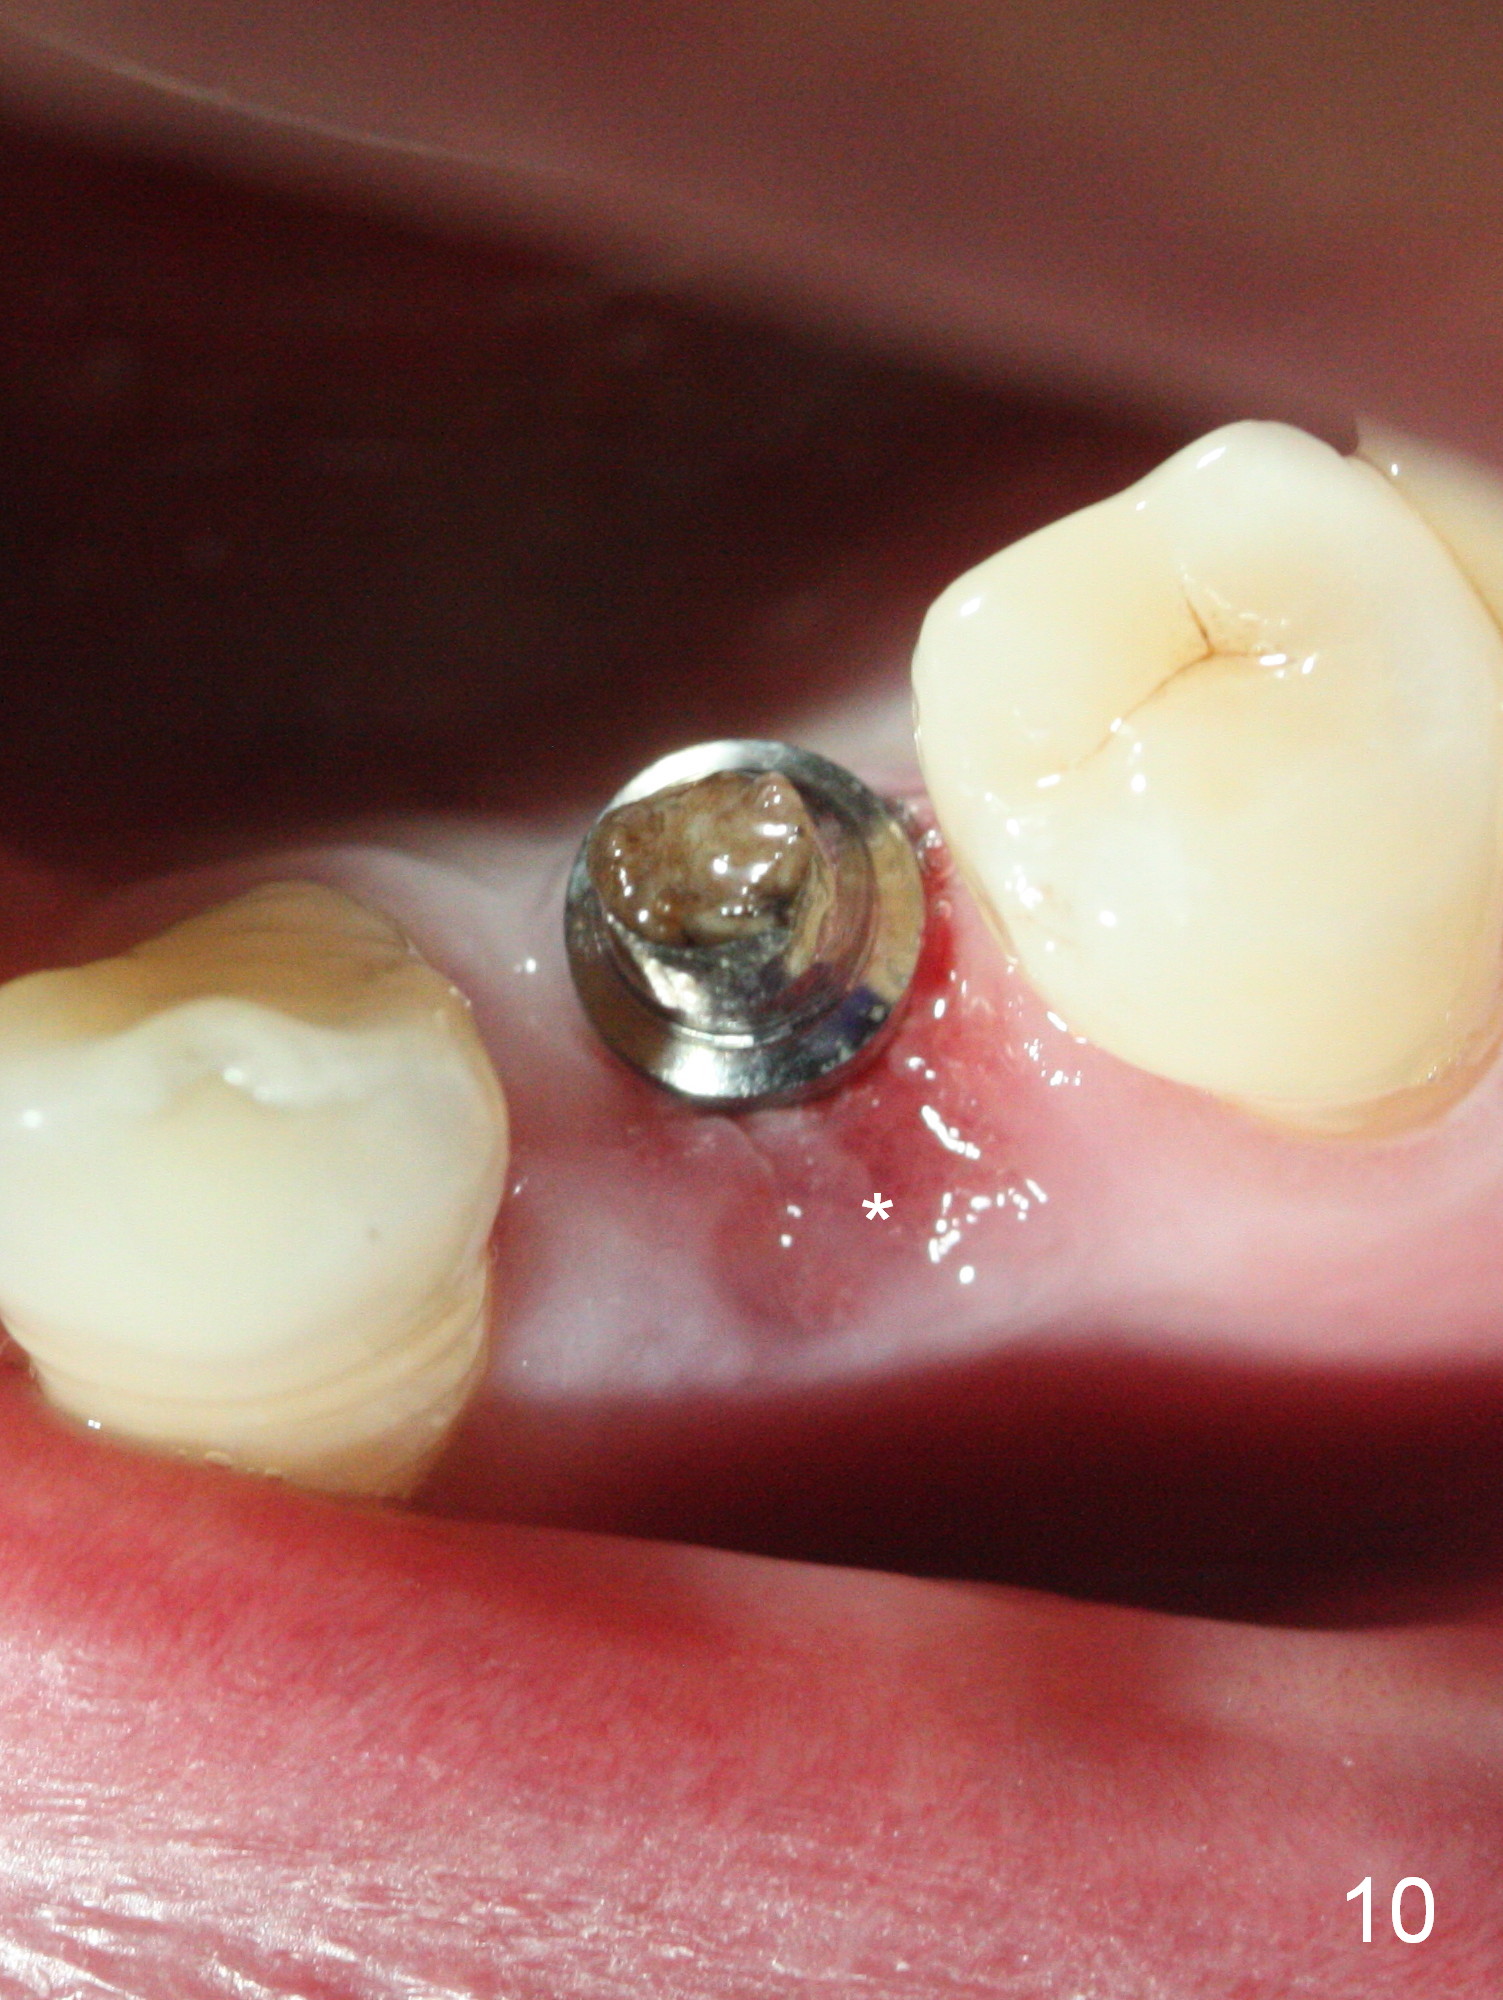

The residual root at #21 seems to be buccally positioned (Fig.1 *). The initial osteotomy is established with the 1.6 mm drill at 11 mm (Fig.2). Later the depth increases to 13 mm. The initial osteotomy is found to be too lingual, but experience shows that as osteotomy increases in diameter, the trajectory would shift buccally due to the thick lingual plate (slope). When 3.3 mm Magic drill reaches 11 mm, the patient feels pain. It is probably due to the dense bone. A 4x11 mm IBS implant cannot be seated due to high torque; it is removed. The osteotomy is increased with 3.8 mm drill. The implant is re-seated with >55 Ncm; it is over-lingually placed. Due to failure to seat the implant driver completely, the implant cannot be un-torqued. A 4.5 mm 15° angled abutment (3 mm cuff) is placed for immediate provisional (Fig.3,4 *).

The implant seems to have osteointegrated 4 months postop (Fig.9). When a permanent crown is fabricated, it should have normal occlusal and buccal contour (from Fig.11 (provisional) to 12 red and black curved lines) as well as the buccal cervical extension (Fig.12 to cover the buccal gingiva (Fig.10 *). If the lingual margin of the abutment is too prominent, return the case and the abutment will be changed to the one with 2 mm cuff (existing 3 mm). The lingual margin of the abutment will be trimmed. The patient is not pleased with the short buccal margin of the crown after cementation (Fig.13). In fact the provisional should have been fabricated so that the its buccal margin should be subgingival and within the gingival outline. It may prevent buccal plate collapse. In fact the crown dislodges 1 year post cementation. The lingual margin is prep lower to increase the abutment height. Impression is taken. Although the access hole is unnecessary for cementation, it acts as an escape hole so that there is no excess cement cervically (Fig.14-18).